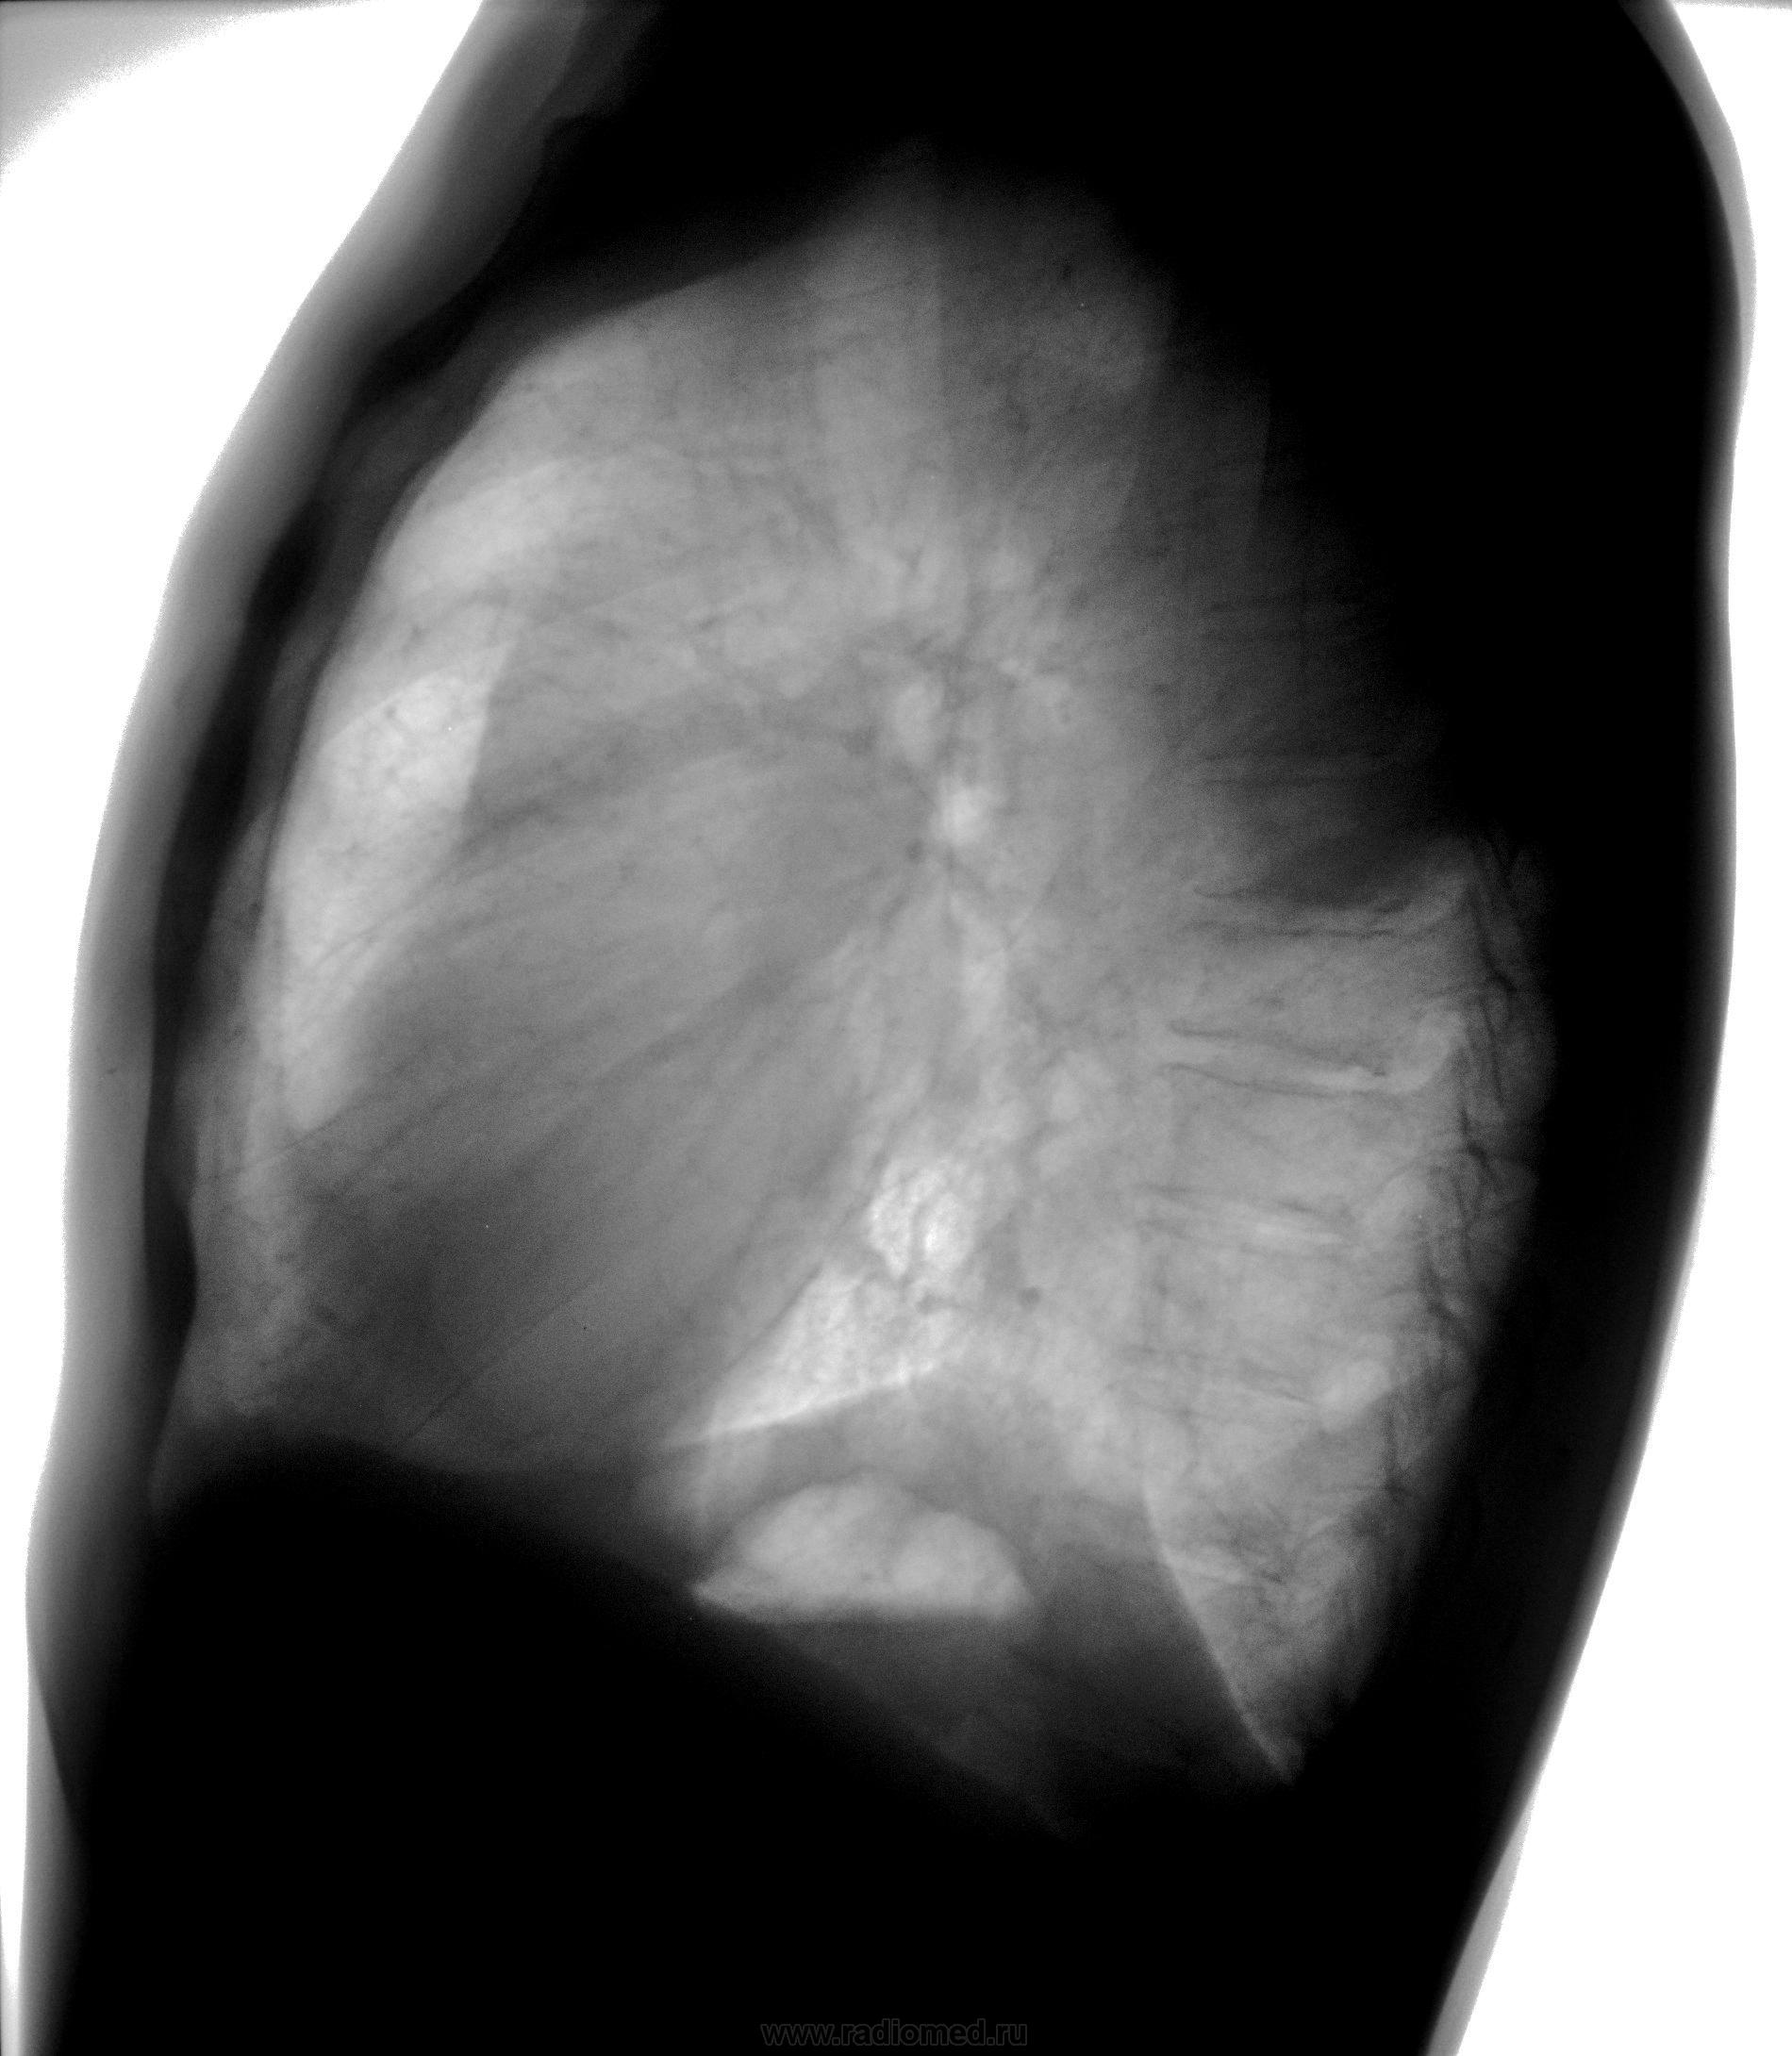

Мужчина 48 лет поступил в клинику с предварительным диагнозом левосторонняя внебольничная нижнедолевая пневмония. Жалобы на общее недомогание в течении 3-4 дней перед госпитализацией, сухой кашель, боли в грудной клетке слева. Объективно субфебриллитет, повышены острофазовые показатели.

Осумкованый паракостальный плеврит.

Не смог разобраться в легком это или в плевральной полости, возможно и плеврит. Или все-таки в легком?

Образование проецируется на шестой сегмент левого легкого

Предлагаю в дифряд мезотелиому.

Если диагностическая ФЛЮ, значит есть отделение и есть аппарат на 3 раб. места. Возьмите и проведите скопию, выведите, снимите, а потом описывайте. Может плеврит, может мезотелиома, может и периферический. Дополнительно анамнез, клиника и анализы.